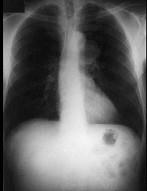

问题 男性,53岁,2年前被踢伤胸部,最近感胸部不适,常规胸片检查,示纵隔内病变,加扫CT平扫及增强,结果如图所示 ( )

选项 A、球形病灶外围见半月形低密度影,其内有斑片状高密度影,考虑为血栓形成 B、结合临床,考虑为主动脉假性动脉瘤(外伤性) C、CT增强扫描示主动脉弓层面左侧缘不规则,造影剂流入球形病灶内 D、结合临床,考虑为主动脉夹层 E、胸片示上纵隔见类圆形高密度影,以侧位片明显

答案 ABCE